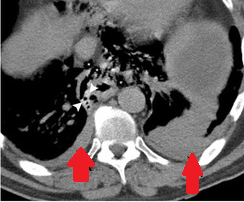

CT θώρακα. Αμφοτερόπλευρες υπεζωκοτικές συλλογές, εντονότερες αριστερά (Ευγενική παραχώρηση Dr. V. Penopoulos)